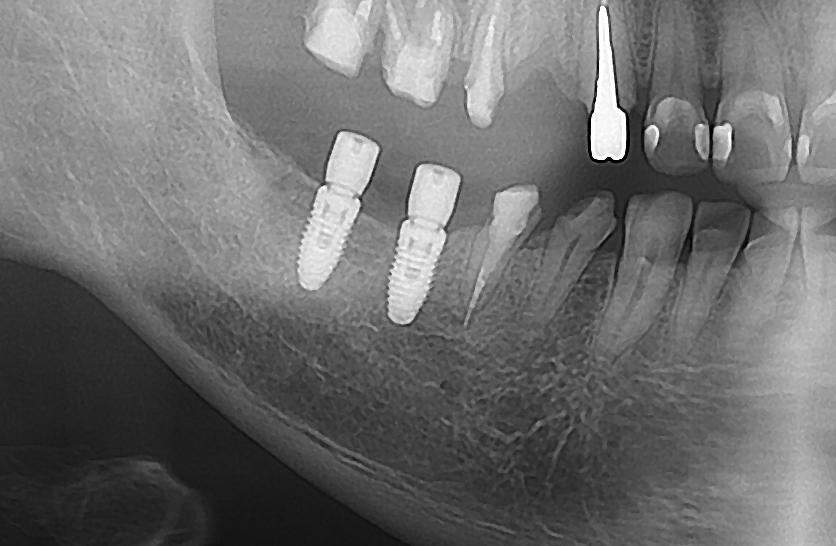

先日行ったインプラント治療を元に説明します。患者さんは右下の奥歯に2本のインプラント治療をご希望されました。歯茎の状態も良く、レントゲン写真では下の骨もしっかりしています。

術前のレントゲン

術後のレントゲン

治療時間は2本で20分で歯茎も切りませんでした。

治療時間の短縮、体に負担が少ない、神経を傷つけるリスクがほぼない、位置が確実